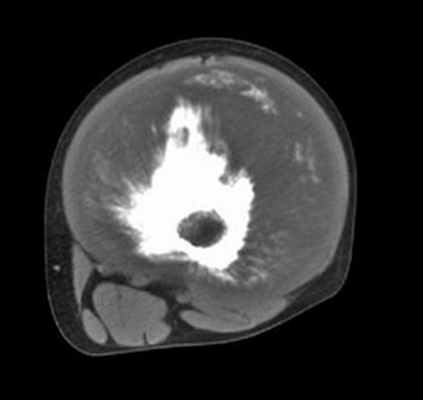

КТ: контур периферического кортикального слоя не прерывается на границе с кортикальным слоем подвздошной кости. Хорошо различимая трабекулярная структура указывает на остеогенный экзостоз.

Свидетельствует о наличии хрящевого обызвествления, захватывающего, по-видимому, соседние мягкие ткани.

TDM Abdomen Axial tissus mous